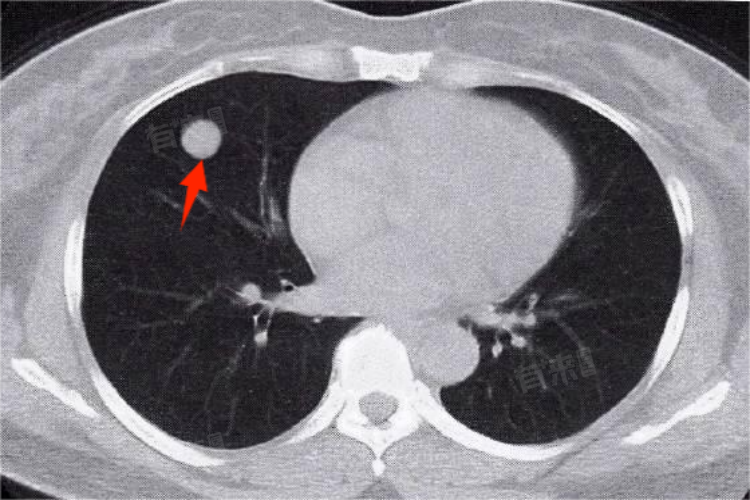

肺占位性病变是医学影像中的常见术语,通常出现在X线、CT等检查结果中,指的是肺部出现不应存在的团块影或球形病变。其严重程度依据病变性质、大小、位置及并发症而异,良性肿瘤多可治愈,恶性肿瘤则视手术及后续治疗情况而定。

- 肺内炎性假瘤是较为轻微的肺占位性病变,通常由肺部炎症引起的局部组织增生所致,其症状较轻,可能包括咳嗽、咳痰等,且病变多为良性,对人体伤害不大。肺结核球是肺结核的一种特殊形态,表现为肺部孤立的圆形或椭圆形阴影,肺结核球可能伴有低热、盗汗等结核中毒症状。虽然肺结核球多为良性,但具有潜在恶变风险,且治疗周期较长。

- 肺部良性肿瘤,如肺腺瘤、肺错构瘤等也是肺占位性病变的一种,肿瘤生长缓慢,对周围组织压迫较轻,通常不会引起严重症状,若肿瘤体积较大或位置特殊,可能影响呼吸功能或压迫邻近器官。肺部恶性肿瘤,如肺癌是肺占位性病变中最严重的类型,早期肺癌可能仅表现为咳嗽、咳痰等症状,但肿瘤生长迅速,易侵犯周围组织及血管,导致咯血、呼吸困难等症状,严重程度相对较低。